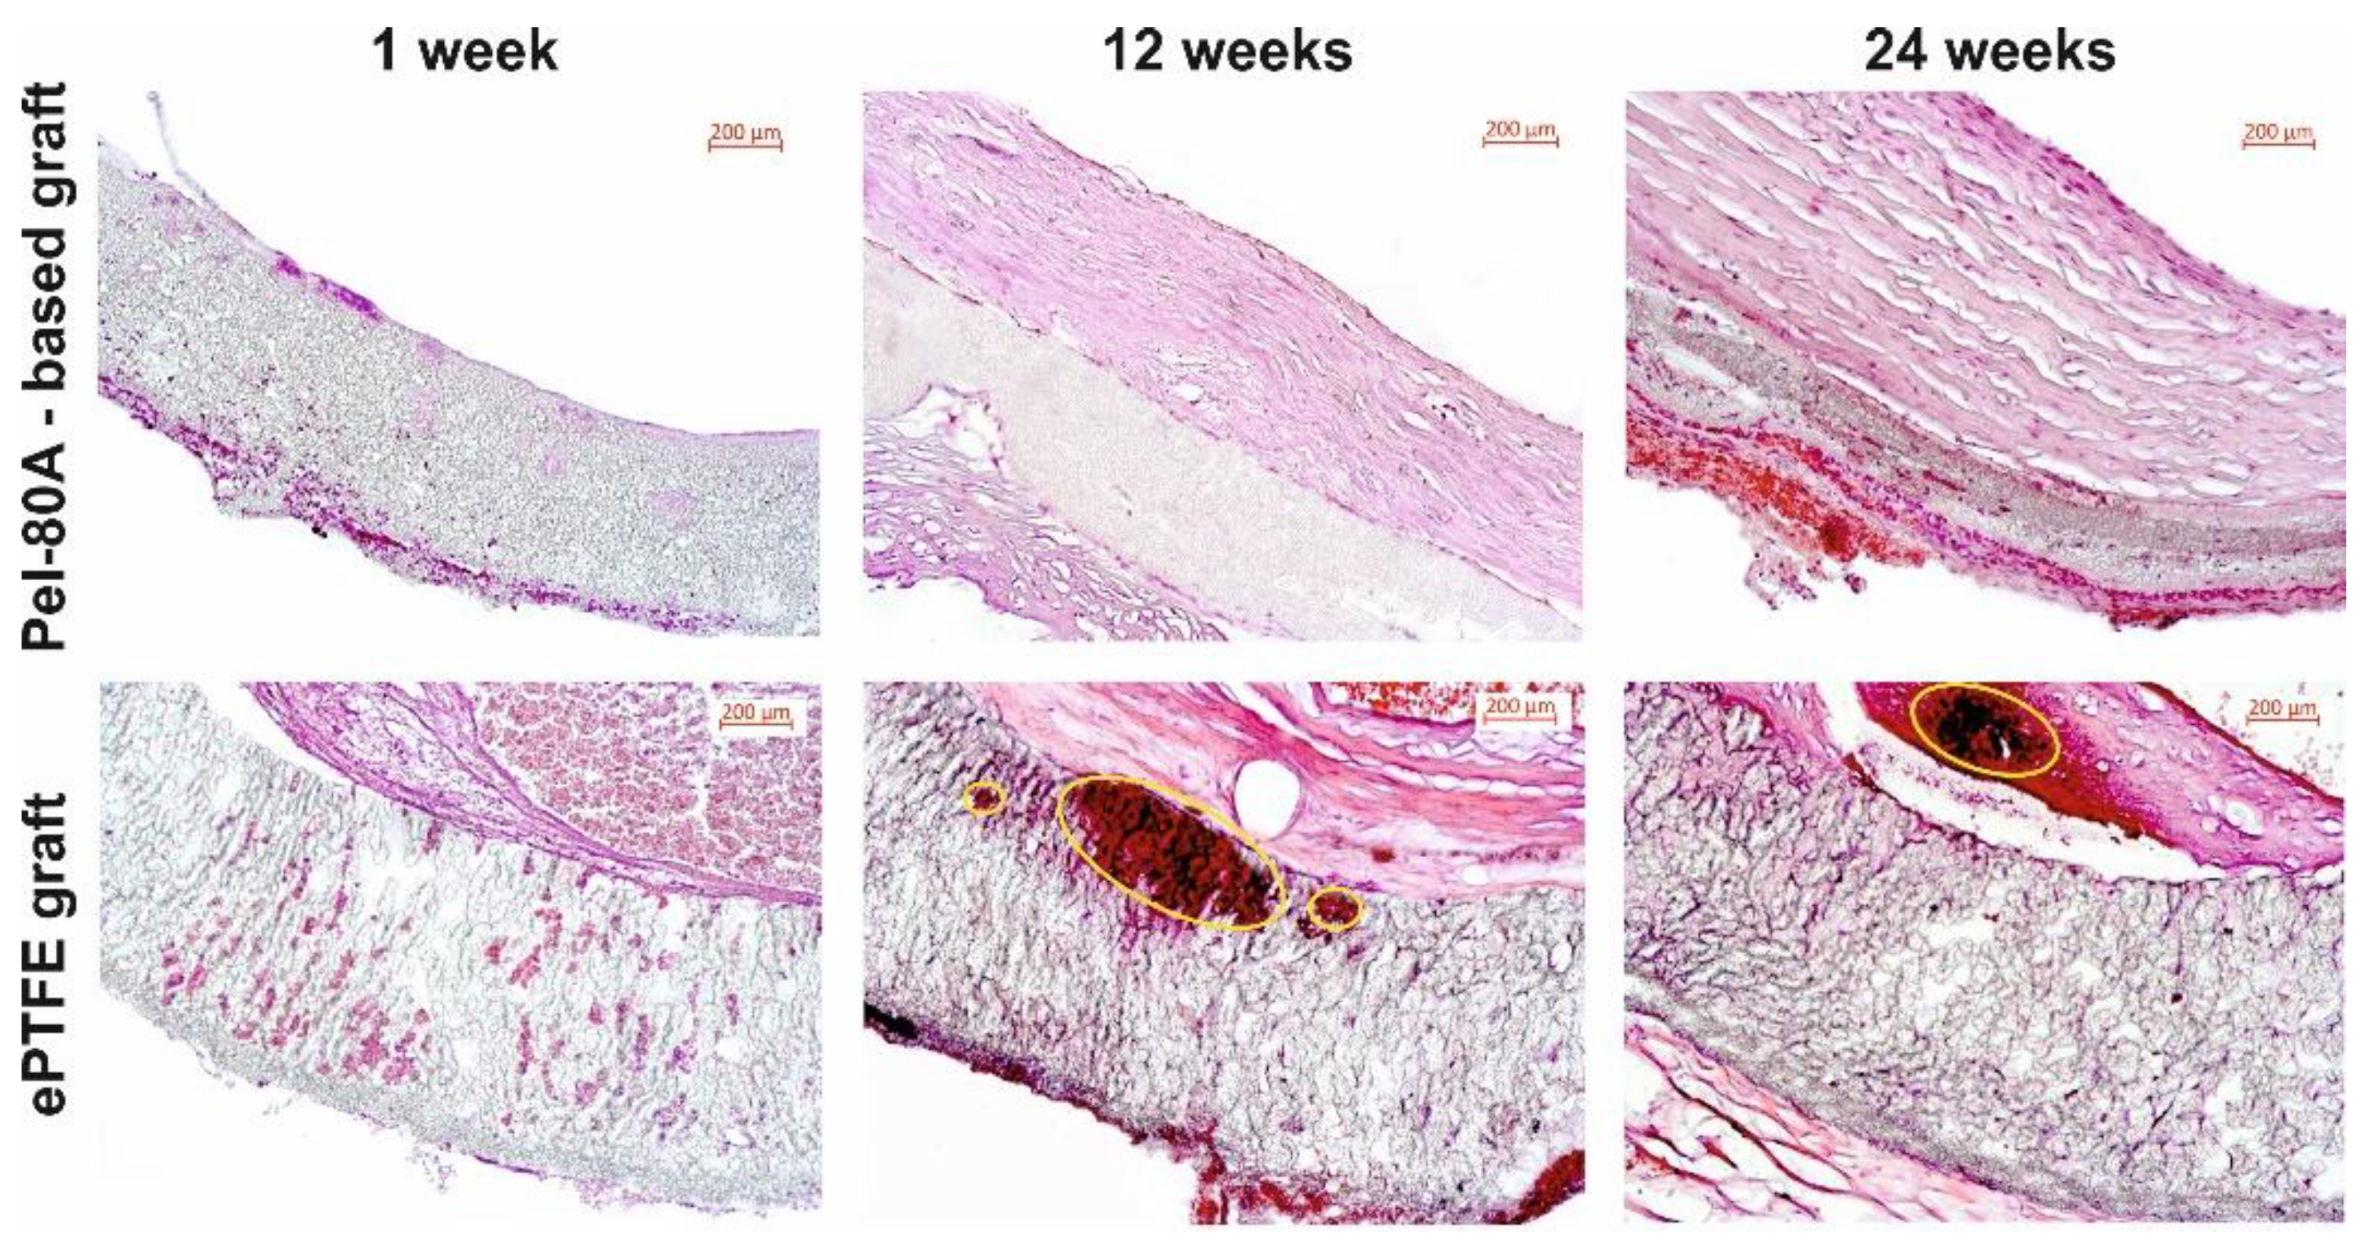

3.3. In Vivo Study of Pel-80A-Based SDVGs

| Studied VGs | Calcification (%) | Thickness of Neointima (µm) | ||||

|---|---|---|---|---|---|---|

| 3 Months | 6 Months | p * | 3 Months | 6 Months | p * | |

| Pel-80A based VGs | 4.55 ± 0.58 | 9.75 ± 0.88 | 0.028 | 41.84 ± 20.21 | 40.22 ± 27.71 | 0.753 |

| ePTFE VGs | 6.36 ± 0.56 | 13.65 ± 1.85 | 0.027 | 40.85 ± 22.21 | 60.76 ± 24.12 | 0.248 |

| p | 0.005 | 0.005 | - | 0.810 | 0.378 | - |